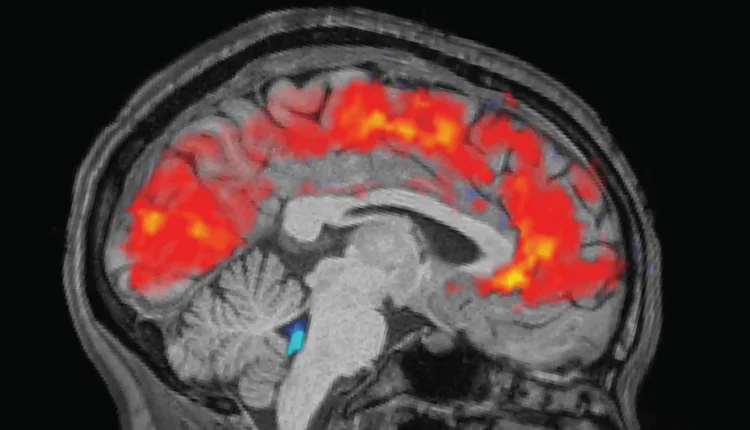

Τα ξεκούραστα άτομα κοιμήθηκαν για 6,5 έως 9 ώρες στο σπίτι, ενώ τα άτομα που στερήθηκαν τον ύπνο έμειναν ξύπνια όλη τη νύχτα στο εργαστήριο. Το πρωί πριν από κάθε δοκιμή, η ομάδα στερέωσε ηλεκτροεγκεφαλογραφικά (ΗΕΓ) καπέλα στους συμμετέχοντες για να καταγράψει τα εγκεφαλικά τους κύματα με ηλεκτρόδια. Ταυτόχρονα, οι συμμετέχοντες υποβλήθηκαν σε σαρώσεις λειτουργικής μαγνητικής τομογραφίας (fMRI) για να αποκαλύψουν μοτίβα στη ροή αίματος και ΕΝΥ στον εγκέφαλο. Οι ανιχνευτές ματιών μέτρησαν το μέγεθος της κόρης των ματιών των συμμετεχόντων.

Όπως αναμενόταν, οι συμμετέχοντες χρειάστηκαν περισσότερο χρόνο για να παρατηρήσουν τα ερεθίσματα όταν ήταν κουρασμένοι και έχασαν τα σημάδια συχνότερα από ό,τι όταν ήταν καλά ξεκούραστοι. Αλλά η ομάδα εξεπλάγη όταν είδε γιγάντιους παλμούς ΕΝΥ στα εξαντλημένα άτομα, παράλληλα με μοτίβα αργών εγκεφαλικών κυμάτων – και τα δύο παρατηρούνται συνήθως στον ύπνο non-REM.

Συγκεκριμένα, τα μοτίβα έμοιαζαν με αυτά που παρατηρούνται όταν ένα άτομο μεταβαίνει από το στάδιο Ν1 στο Ν2, τα δύο πρώτα από τα τρία στάδια ύπνου non-REM που βιώνουν οι άνθρωποι κατά τη διάρκεια κάθε ύπνου. “Αυτό ήταν κάτι που προηγουμένως είχαμε δει σε αυτή την κλίμακα μόνο κατά τη διάρκεια του ύπνου”, δήλωσε η Lewis.

Η ροή του ΕΝΥ συνδέθηκε στενά με το μέγεθος της κόρης του ματιού, με τη μεγάλη εισερχόμενη ροή να ακολουθεί τη διαστολή της κόρης και την εξερχόμενη να έρχεται μετά τη συστολή της κόρης. Αυτή η σύνδεση ήταν πιο έντονη στα άτομα που είχαν στερηθεί τον ύπνο, γεγονός που θα μπορούσε να υποδηλώνει ότι το κυκλοφορικό σύστημα του σώματος στηρίζει αυτή τη σύζευξη, έγραψαν οι συγγραφείς. Οι ροές του ΕΝΥ συνέπεσαν επίσης με τις στιγμές που τα άτομα “έχαναν” την προσοχή τους κατά τη διάρκεια των εργασιών.

Οι ερευνητές πιστεύουν ότι τα εγκεφαλικά μοτίβα που βλέπουν μπορεί να αντανακλούν τον εγκέφαλο που έχει στερηθεί τον ύπνο και μεταβαίνει σε μια κατάσταση παρόμοια με τον ύπνο, αλλά ενώ είναι ακόμα ξύπνιος. Οι διακοπές στην προσοχή σηματοδοτούν την έναρξη αυτών των εγκεφαλικών διεργασιών που μοιάζουν με ύπνο, αλλά διακόπτονται πριν αρχίσει ο κανονικός ύπνος.